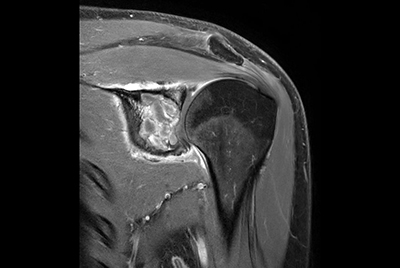

Push-button Shoulder exam, under 5 minutes